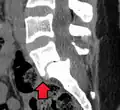

(A) CT sagittal view of a low grade slip.

(B) Lateral radiograph pre-operative intervention.

(C) Surgically treated with L5–S1 decompression, instrumented fusion and placement of an interbody graft between L5 and S1.